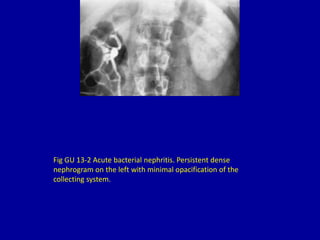

A persistent or increasingly dense nephrogram on imaging can indicate several potential issues: 1) Acute urinary tract obstruction, as shown by a prolonged nephrogram and no calyceal filling, often due to a kidney stone blocking the ureter. 2) Acute bacterial nephritis, seen as a persistent dense nephrogram with minimal collecting system opacification. 3) Acute renal failure, seen on an excretory urogram as bilateral persistent nephrograms with no calyceal filling 20 minutes after contrast injection. 4) Acute renal vein thrombosis, appearing as a dense nephrogram and absence of calyceal filling 5 minutes